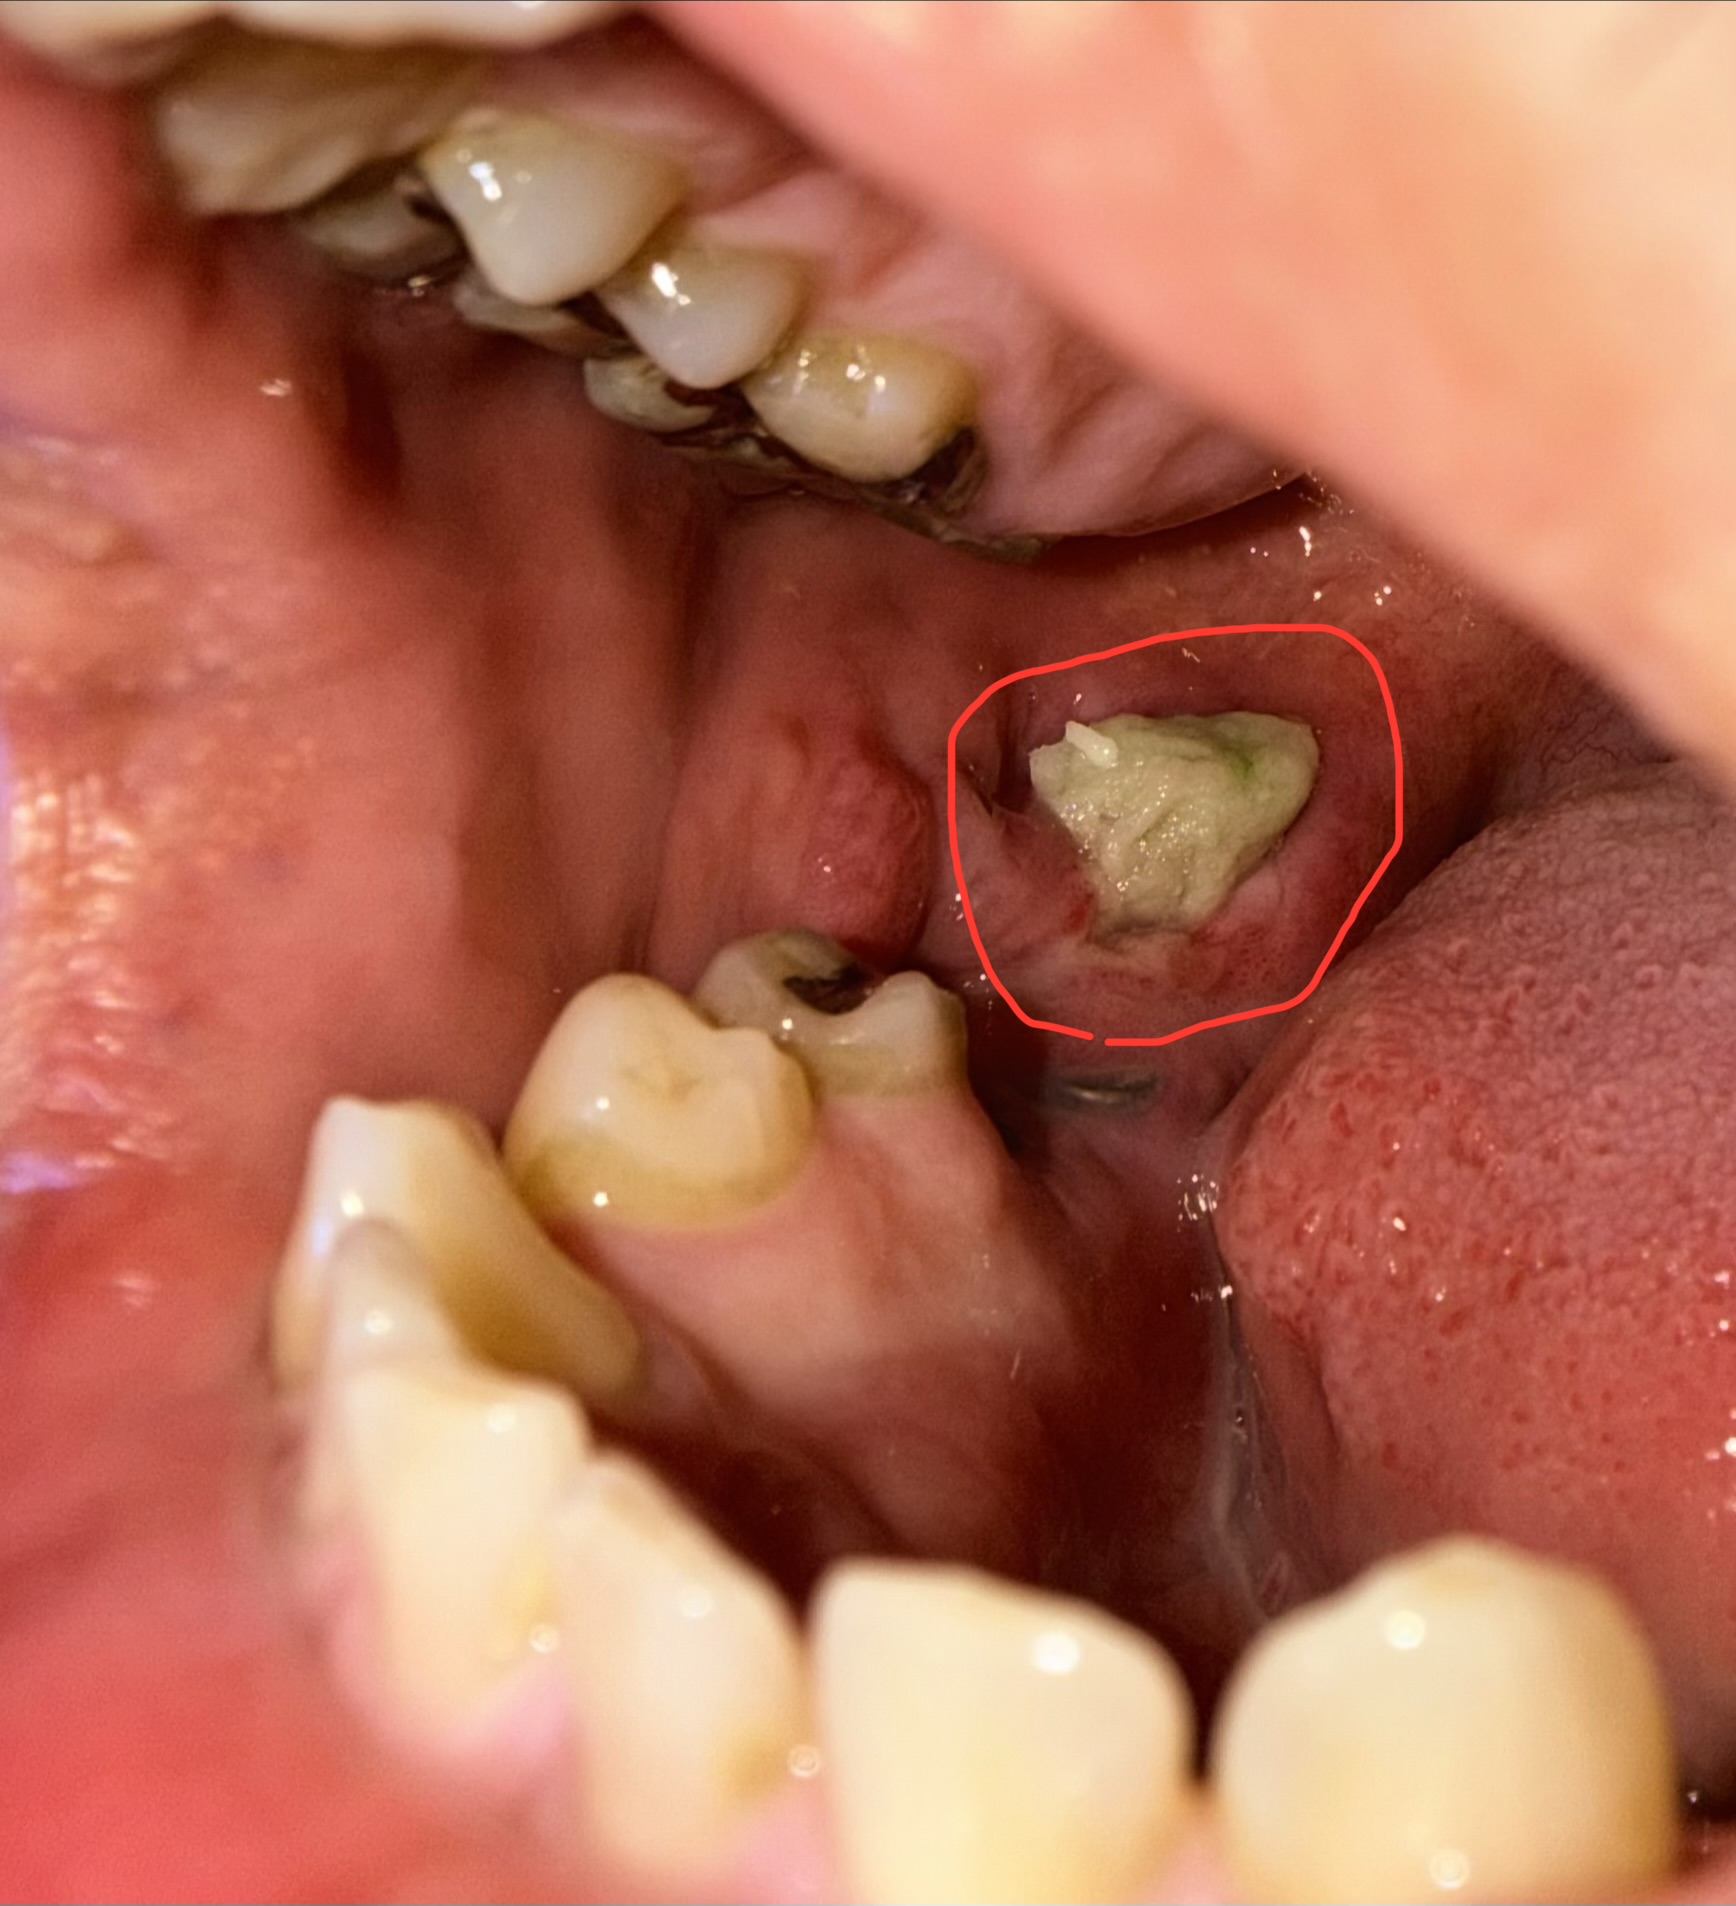

親知らず抜歯後、歯茎から白くて柔らかい物が出てきました。

親知らず抜歯後、奥に白い物が見えます。